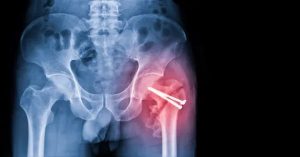

Cerrahi yöntemler en sık tercih edilen yaklaşımdır. Total veya parsiyel kalça protezi, kırığın yerine ve kemiğin durumuna göre seçilir. Vida ile fiksasyon, özellikle femur boynu ve intertrokanterik kırıklarda uygulanır. Cerrahi, hastanın kısa sürede ayağa kalkmasını sağlar. Uzun süre yatakta kalmanın getirdiği pıhtı ve kas erimesi riski azalır.